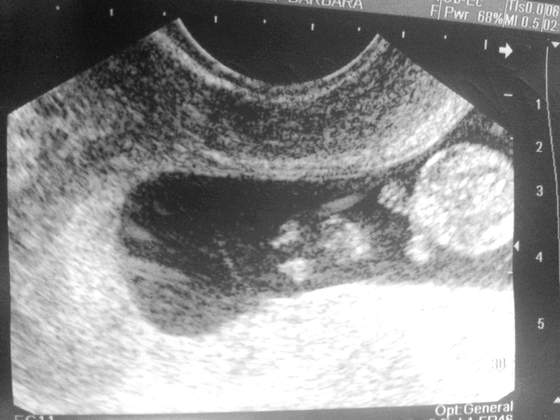

Tak jak obiecalam dziewczyny. Kolejne fotki mojej modelki/ modela ♡ Z dzisiaj tj. 9+2. Moja nowa milosc ma 27,05mm :-):-):-)

Zobacz załącznik 564201Zobacz załącznik 564200